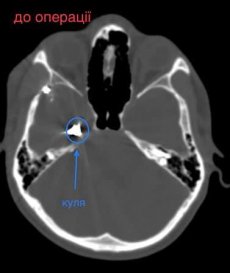

У Волинській обласній дитячій клінічній лікарні прооперували 16- річного юнака з травмою головного мозку. І травма ця дуже незвичайна – у хлопця була куля в голові, що призвела до руйнації скроневої кістки та частини головного мозку.

Лікарі виконали невідкладну операцію і вилучили стороннє тіло, видалили пошкоджені тканини і відновили цілісність збережених тканин.

«Добре, що куля зупинилась в 1 см від надзвичайно важливої судини і права скронева частка (яка пошкодилась в результаті травми) - функціонально незначима. Інакше, наш козак був би зовсім іншим, навзавжди», - пише лікар.